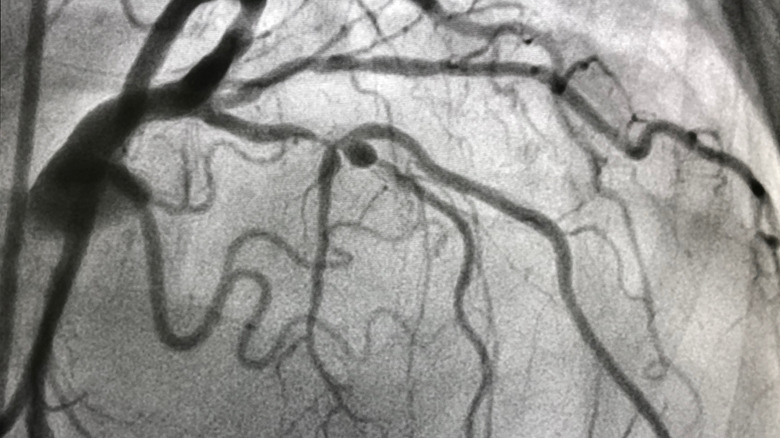

Excess cholesterol circulating in your blood can cause "plaque" to form in your circulatory system, per the CDC. When plaque builds up, it can interfere with optimal circulation (via Beaumont Health). There are no known symptoms of plaque buildup, but when it reaches a critical mass, so to speak, then you may experience symptoms of atherosclerosis, which Mayo Clinic defines as "the buildup of fats, cholesterol, and other substances, in and on your artery walls," that causes the narrowing and stiffening of the arteries. Atherosclerosis is also known as coronary artery disease (CAD), coronary heart disease, and ischemic heart disease. Whatever you may wish to call it, the CDC says it's the most common type of heart disease in the U.S.